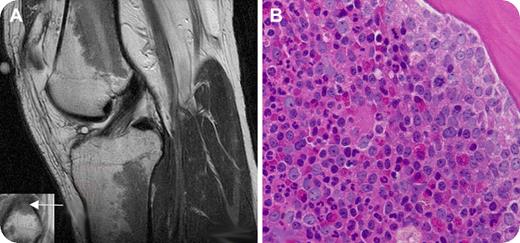

Laboratory tests showed a white blood cell count of 25.3 × 109/L with 55% neutrophils, 8% bands, 5% myelocytes, 6% metamyelocytes, 21% lymphocytes, 4% monocytes, and 1% basophils; hematocrit of 43.7%; and platelet count of 203 × 109/L. A bone marrow aspirate and biopsy from the left posterior-superior iliac crest revealed hypercellularity with granulocytic predominance (panel B). Karyotypic analysis revealed a Philadelphia chromosome (t (9;22)). The patient was diagnosed with chronic myelogenous leukemia (CML) and therapy with imatinib mesylate was initiated.